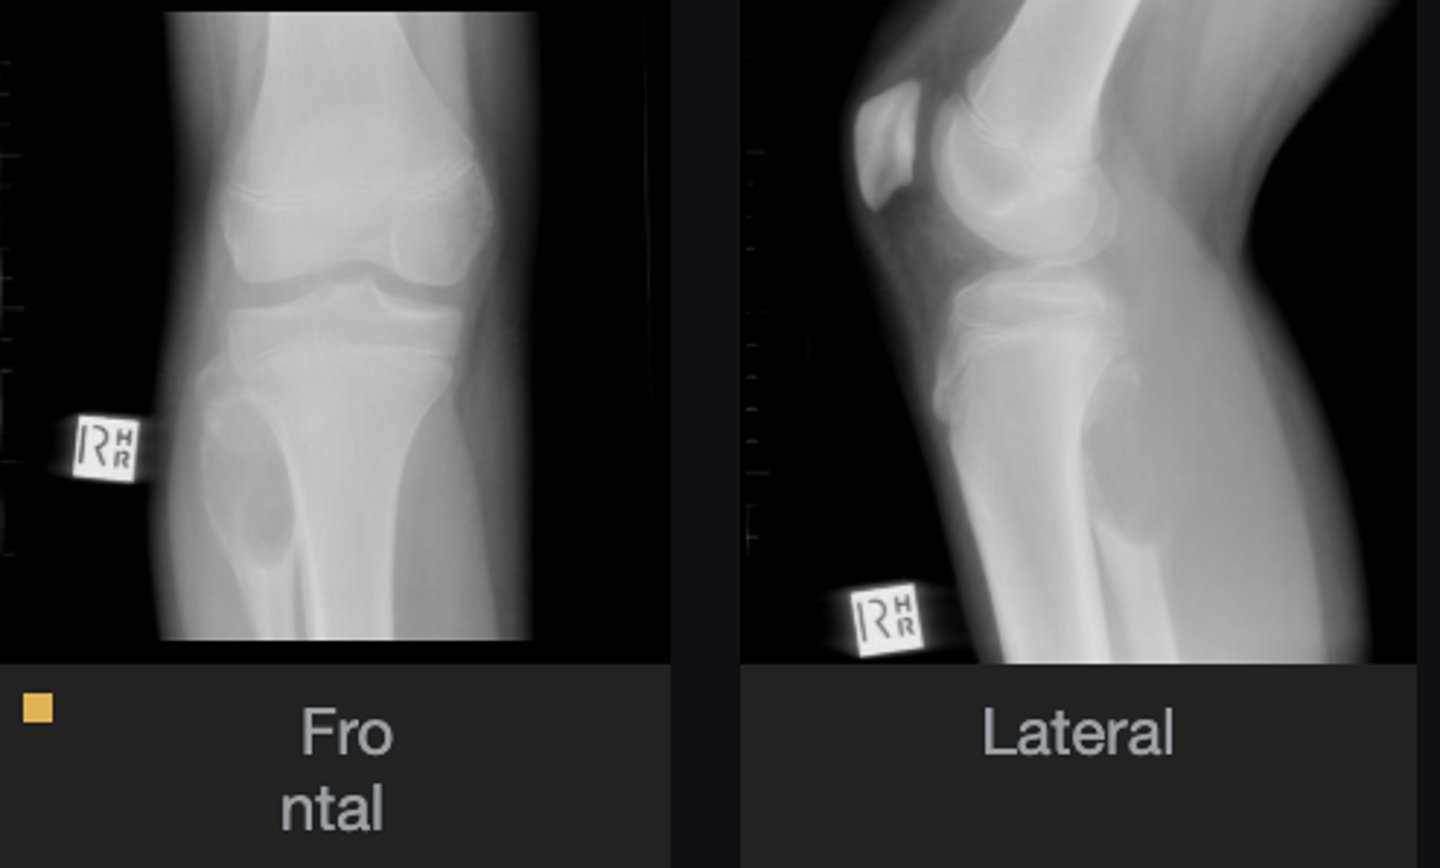

Lateral proximal tibia

Bone

<p>Bone</p>

- Longitudinal: epiphysis/metaphysis (up to joint surface)

- Eccentricity: eccentric

- Transverse: medullary

Location

<p>Location</p>

- Lytic

- Geographic

- Short zone of transition

Behavior

<p>Behavior</p>

- Cortical thinning

- Cortical expansion

Cortex

<p>Cortex</p>

Nothing visible

Matrix

<p>Matrix</p>

Joint surface involved

Joint involvement

<p>Joint involvement</p>

Giant cell tumor

Most likely diagnosis?

<p>Most likely diagnosis?</p>

Refer to orthopedist or oncologist

Next step?

<p>Next step?</p>

Could be aggressive (20%)

Concerns/complications?

<p>Concerns/complications?</p>